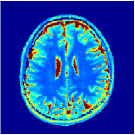

VI-E In-vivo experiments

Two sets of experiments were conducted here: first, we used the 2D and 3D acquisition sequences for scanning a healthy volunteer’s brain (real-world acquisitions). Figures 6 and 7 display the parametric maps reconstructed from 2D spiral and radial readouts. We computed the T1, T2 and proton density (PD) maps using baseline reconstruction algorithms ZF, VS, LR, FLOR, AIR-MRF and our proposed LRTV. While baselines use DM either for quantitative inference or also during reconstruction (i.e. AIR-MRF), we further compare the DM-free LRTV’s performance when cascaded to DM, KM and MRFResnet for quantitative inference. For the 3D spiral acquisitions we compared LRTV and its closest competitor VS in Figure 8. Outcomes from other tested algorithm are displayed in the supplementary materials (Figure S5). Since FLOR does not use dimensionality-reduction, our system ran out of memory during 3D reconstruction; hence results are not reported in this case.

VI-E1 Discussion

The LRTV-DM and LRTV-MRFResnet perform on par, and both outperform all tested baselines for reconstructing T1, T2 and PD maps in all acquisition schemes. This can be observed both visually in Figures 6, 7, 8, S2 and S3, and quantitatively in Table IV across all tested metrics. Other baselines were unable to successfully remove the under-sampling artefacts in TSMIs, and these errors propagated to the parameter inference phase and resulted in inaccurate maps. Temporal-only priors incorporated within LR are shown insufficient to regularise the inverse problem and LR sometimes (e.g. 2D spiral acquisitions) can admit solutions with even stronger artefacts than the model-free ZF baseline. This issue was previously studied for other non-Cartesian MRF readouts that similar to our spiral/radial trajectories, miss to sample the corners of the k-space in all timeframes (see section 2.2.2 and figure 2 in [19]). In the absence of reference for the k-space corners information, the LR iterations despite minimising the objective can converge to solutions with high-frequency artefacts, as visible in the computed maps. This highlights the need for adding an appropriate spatial-domain regularisation. FLOR reduces the LR’s artefacts but this improvement is limited because the suggested nuclear norm penalty does not incorporate an explicit spatial regularisation. Further for reducing artefacts, FLOR can introduce an undesirable bias in the computed T1/T2 maps e.g. see error maps in Figures S2 and S3. The non model-based VS baseline incorporates spatial regularisation and results in spatially smoother maps than ZF and LR, but it is unable to output artefact-free images. Further and consistent with our in-vitro experiment, we observe that VS overestimates the T2 values (e.g. in White and Grey matter regions) in tested 2D acquisitions i.e. the spatial regularisation trades off agains the quantification accuracy. The model-based AIR-MRF adds spatial regularisation through 2D/3D low-pass Gaussian filters however this trades off the sharpness of the computed maps and can increase the errors at the tissue boundaries (we searched Gaussian spreads that keep the blurs and high-frequency artefacts minimal). For our acquisition readouts, Gaussian filters performed better than disk filters of [19] for avoiding strong Gibbs artefacts. On the other hand, the spatiotemporally regularised LRTV greatly improves the TSMI reconstructions i.e. 4 dB enhancement compared to the closest competitor baseline (Table IV). This enables computing accurate and aliased-free multi-parametric inference using DM or the DM-free learning-based alternative MRFResnet as visible in Figures 6, 7, 8, S2 and S3. MRResnet and DM score competitive quantitative inference results i.e. T1 and T2 MAPE less than 5% and 9%, respectively (Table IV). KM also outputs comparably accurate T1 maps, however this shallow learning model despite having a model size larger than MRFResnet, is unable to learn accurate T2/PD quantification and it results in poor estimated maps, consistent with our observations in section VI-C.